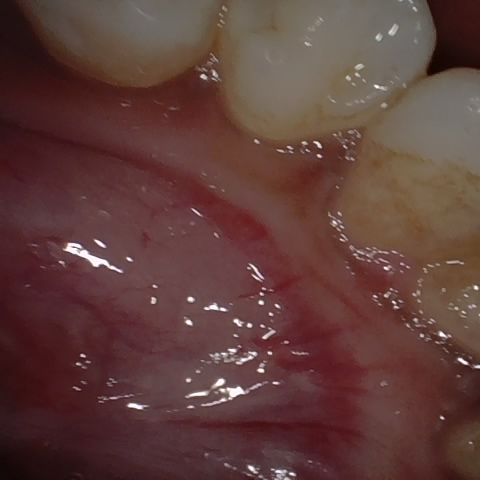

NHD9283

Annotated as "Good"